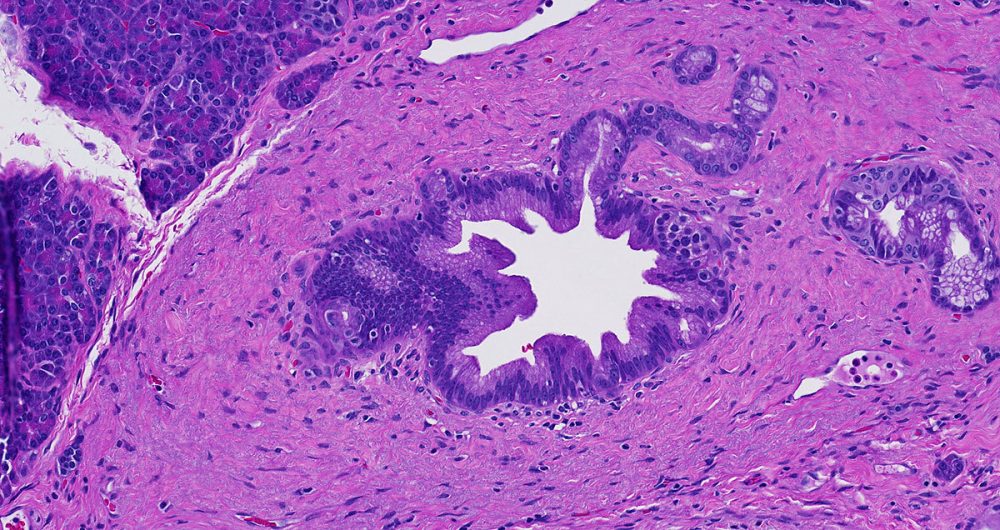

Low-grade pancreatic intraepithelial neoplasia encompasses three older terms- PanIN-1A, PanIN-1B and PanIN-2.